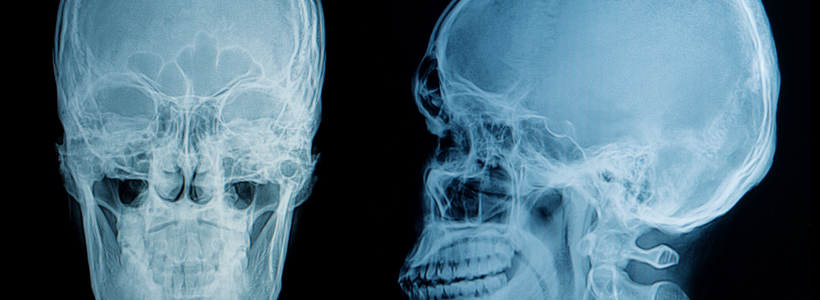

Traumatic Head injuries are one of the main causes of disability or death. Regardless of whether or not you believe the injury to be severe or minor, you should always consult a medical professional to make sure that you or a loved one is ok. When you’re hurt and suffering from debilitating injuries, you need professional help to make sure you get 100% of what you need.

Head Injuries can be hard to notice, and a person with a head injury often shows no outward appearance of being injured. Brain injuries, unlike broken bones, can have lasting and serious consequences if not seen to immediately. Often, those who are suffering from traumatic brain injuries also aren’t aware that their other functions are also being impaired by the injury.

- Fractures – This is a break in the thick skeletal bone. This type of head injury can be more severe because more force is required to break the thick skull bone. In most cases, severe brain damage does occur.

- Linear Skull Fractures – This is one of the more common skull fracture types. There is a broken area in the skull, but the bone is still in the spot it should be. Typically, little intervention is needed to correct this injury.

- Depressed Skull Fractures – This is one of the more traumatic brain injuries as the brain itself is subject to damage. At this level, severe loss of motor function is possible, as well as extended comas.